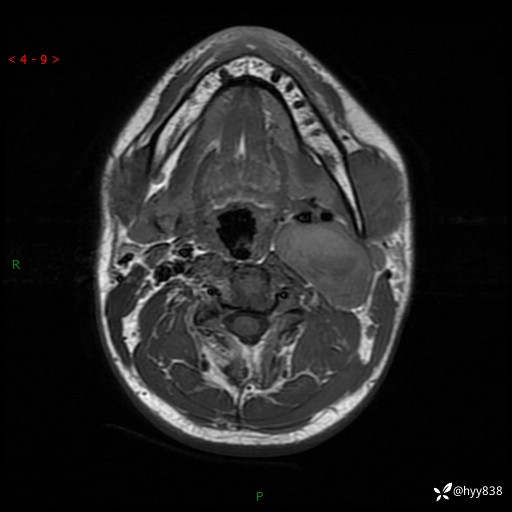

年轻小伙,发现左侧颈部肿物3年余,逐渐增大---结果公布~

现病史:患者约3年前因感冒发现左侧颈部长一肿物,约半个鸡蛋大小,无明显疼痛及其他不适,一直未行特殊处理。3个月前发现左侧颈部肿物变大,随后至当地市第二人民医院耳鼻喉科行左侧颈部彩超示:左侧颈部囊实混合性包块;喉部MPR示:左侧胸锁乳突肌内前方占位,累及左侧喉旁间隙,建议增强扫描。建议手术治疗。患者考虑。随后至我院肿瘤科就诊,行细胞学穿刺示:考虑血管源性肿瘤可能,建议进一步检查。建议至我院口腔科就诊,行颌面部MRI示:左侧颌下腺后方团状异常信号灶,建议增强。建议手术治疗。为求进一步治疗,门诊以“左侧颈部肿物”收入院。 起病以来,患者神志清、精神良好,饮食睡眠良好,大小便正常,体重未见明显变化。

颈部MRI平扫+增强